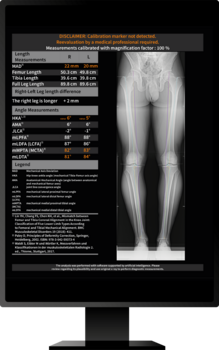

Die zugrunde liegende Technologie der Software von ImageBiopsy Lab basiert auf maschinellem Lernen – also darauf, dass Computer aus Beispielen vorheriger Fälle lernen. Tausende Röntgenbilder, von Ärzt*innen manuell markiert, dienen als Trainingsdaten: Sie zeigen der Software, wo etwa Gelenkspalten, Knochenwinkel oder Brüche liegen. Das System lernt, ähnliche Strukturen in neuen Bildern automatisch zu erkennen und zu vermessen. Die Lösungen von ImageBiopsy Lab erkennen in Sekundenschnelle relevante Strukturen, messen definierte Parameter und erzeugen einen strukturierten Analysebericht – standardisiert und reproduzierbar. So entsteht eine belastbare Grundlage für Diagnostik, Verlaufskontrolle und Therapieentscheidungen.

Heute hat ImageBiopsy Lab sieben zertifizierte Module ((MDR/TÜV SÜD, teil auch von der US-FDA) auf dem Markt. Sie decken zentrale anatomische Regionen wie Knie, Hüfte, Wirbelsäule oder Fuß ab und liefern standardisierte Analyseberichte, die in radiologischen und orthopädischen Praxen in Deutschland, Österreich und der Schweiz eingesetzt werden. Installiert „on-premise“ laufen sie im Hintergrund und liefern Zusatzinformationen direkt zum Bild.